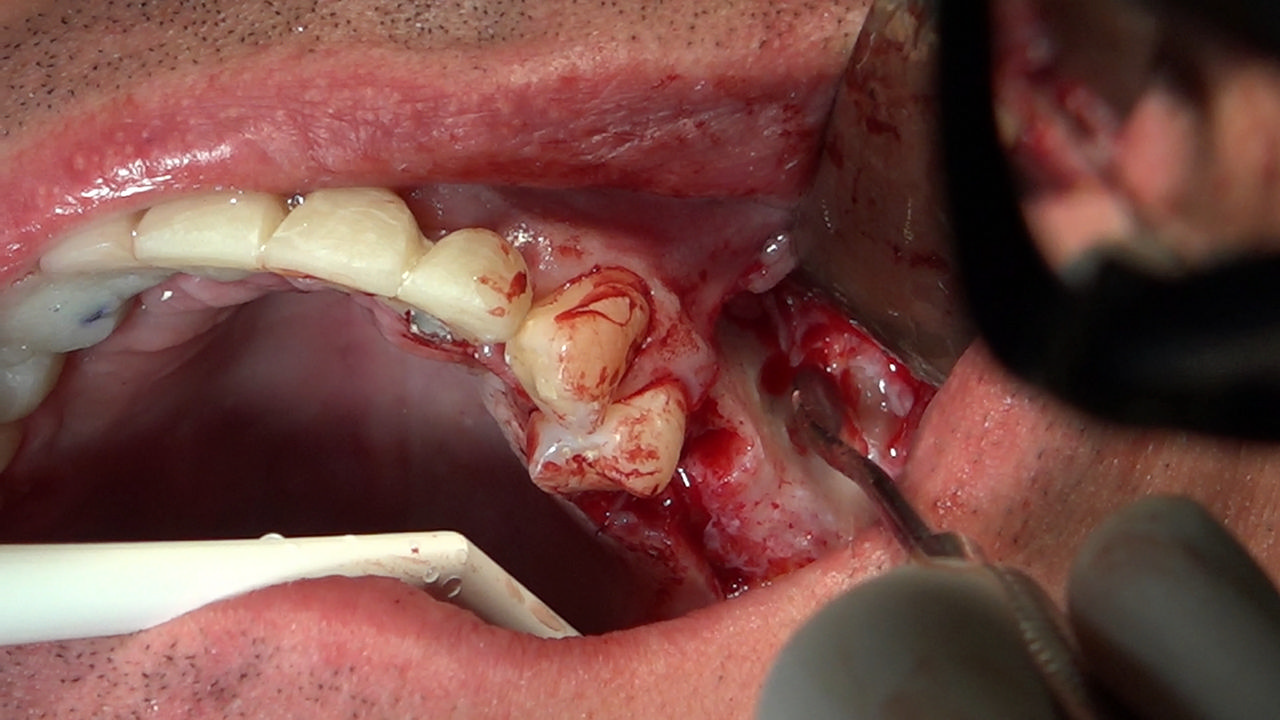

PRACTICULUM IMPLANTOLOGII - SEZON X - SESJA 7

7 Sesja X Sezonu Practiculum Implantologii, w której brali udział kursanci z Grupy A i B, obejmowała implantacje wykonane systemem Axiom, procedury regeneracyjne tkanki kostnej i zabieg sinus lift oraz procedury implantoptotetyczne. Ten zakres szkolenia poprowadziła dr Małgorzata Piotrowska. Protetyka na implantach, to finalny etap leczenia implantologicznego decydujący o uzyskaniu harmonijnego łuku zębowego, okluzji oraz szczelności połączeń, a więc zadowoleniu Pacjenta i powodzeniu całego procesu leczenia.

Jego sednem jest wybór optymalnego rozwiązania rekonstrukcji protetycznej uwzględniający bardzo wiele czynników o charakterze mechanicznym, funkcjonalnym i estetycznym, związanych ze stanem tkanki kostnej, jamy ustnej i uzębienia. Odbywa się już na etapie tomografii komputerowej i jest ściśle powiązany z częścią chirurgiczną, ponieważ prawidłowe zaplanowanie pracy i usytuowania implantów wspomagane plastyką tkanek miękkich, to dla procedur protetycznych baza wyjściowa. Zasady te są jak najbardziej oczywiste, zarówno przy samodzielnym wykonywaniu leczenia implantologicznego, jak i przy podziale zadań dla chirurga i protetyka, czyli pracy w duecie.